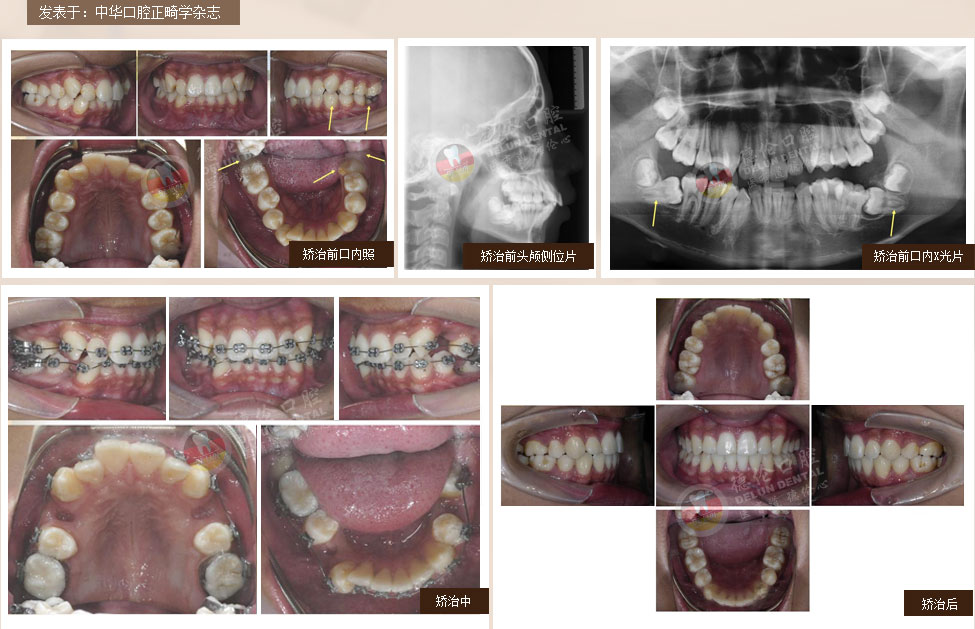

• 女:24歲

癥狀:牙列不齊、下頜第二、第三磨牙水平阻生,左側磨牙鎖牙合

矯治方法:拔除上頜及右下第一雙尖牙,左下第二雙尖牙以及2個下第三磨牙